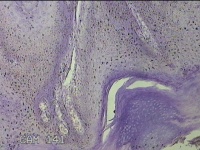

后颈部皮肤结节

性别

男

年龄

45岁

临床诊断

皮肤结节病

一般病史

发现后颈部皮肤结节半年余。

标本名称

大体所见

灰白粉红色组织1.7x0.9x0.3cm一块,表面带梭形皮肤1.7x0.9cm,皮下见结节1.5x1.1cm一个,切开结节呈实性,切面灰白粉红色,质软。